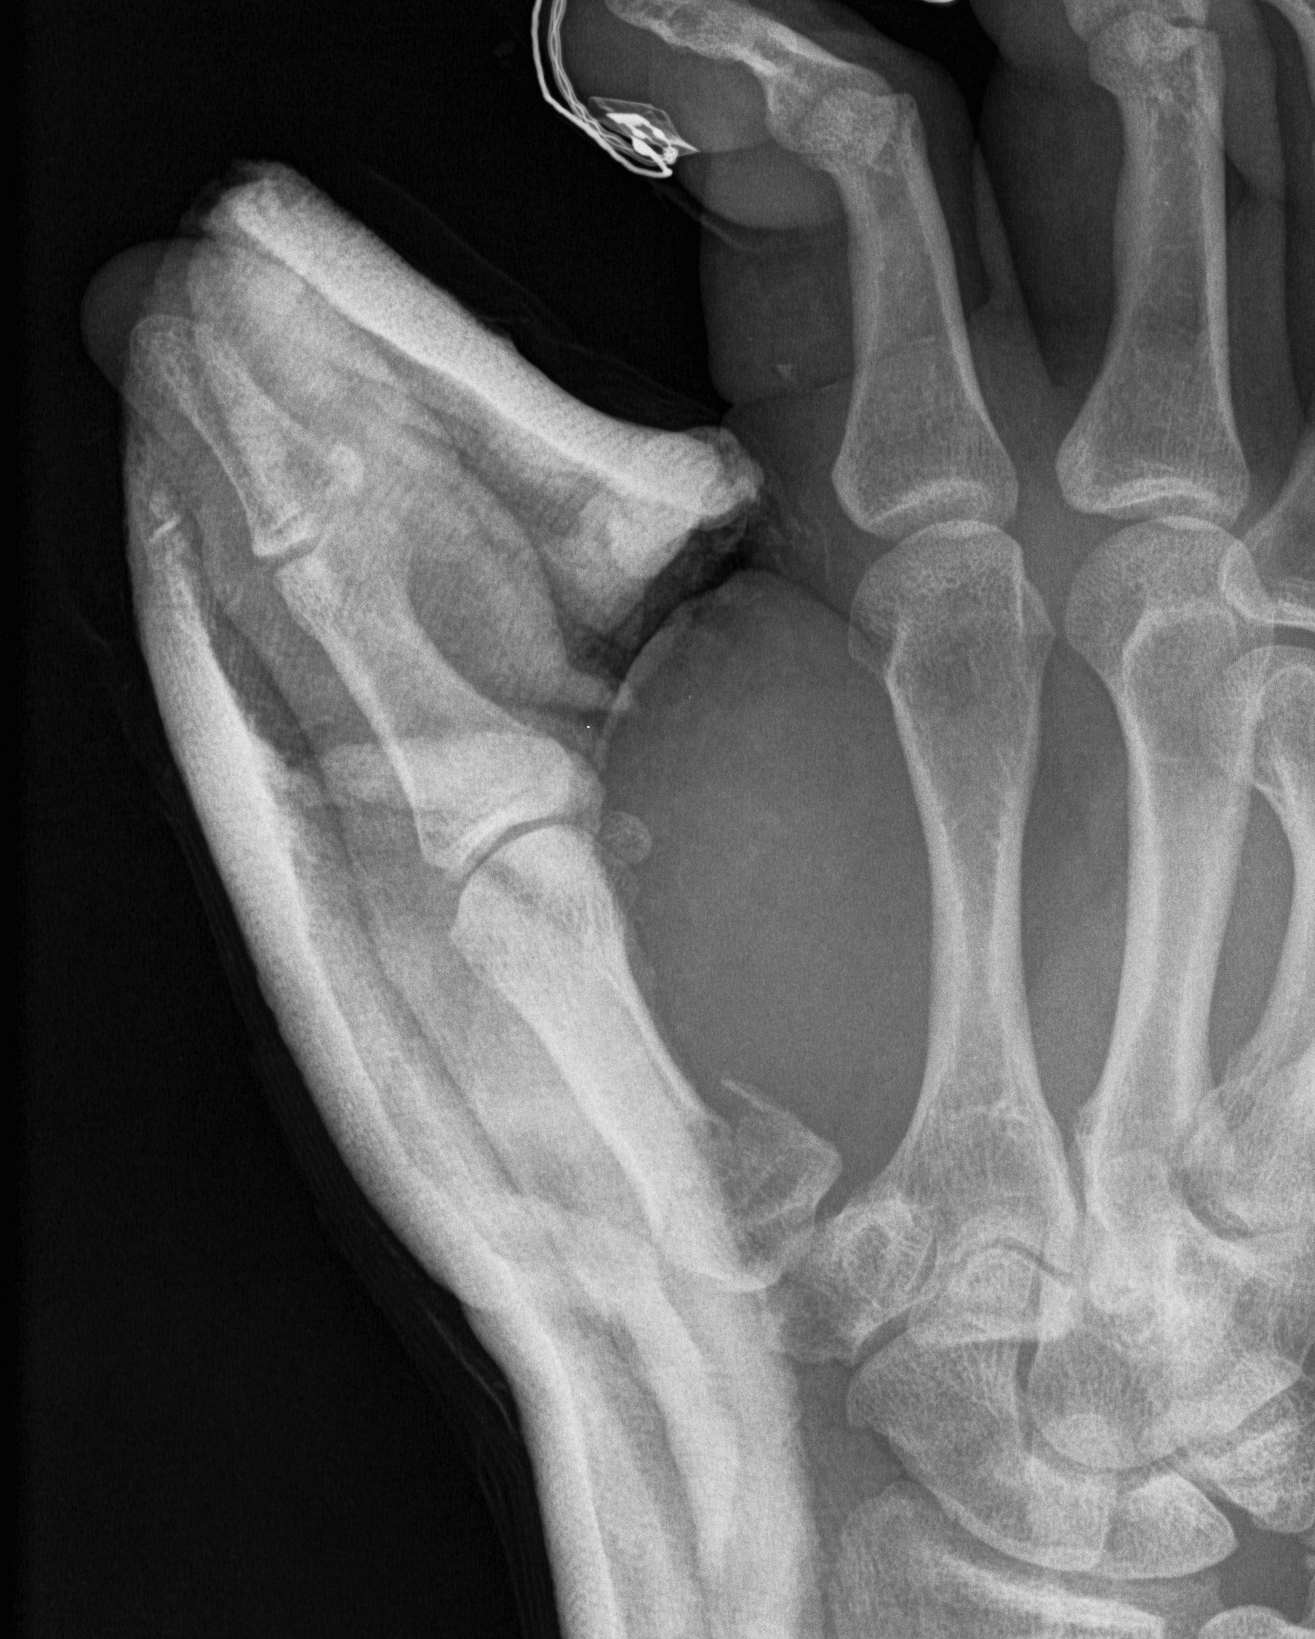

A. Bennett's Fracture

Fracture

- oblique intra-articular fracture

- small volar fragment remains in situ as attached to beak ligament

- metacarpal displaces proximally and dorsally due to APL

- inherently unstable